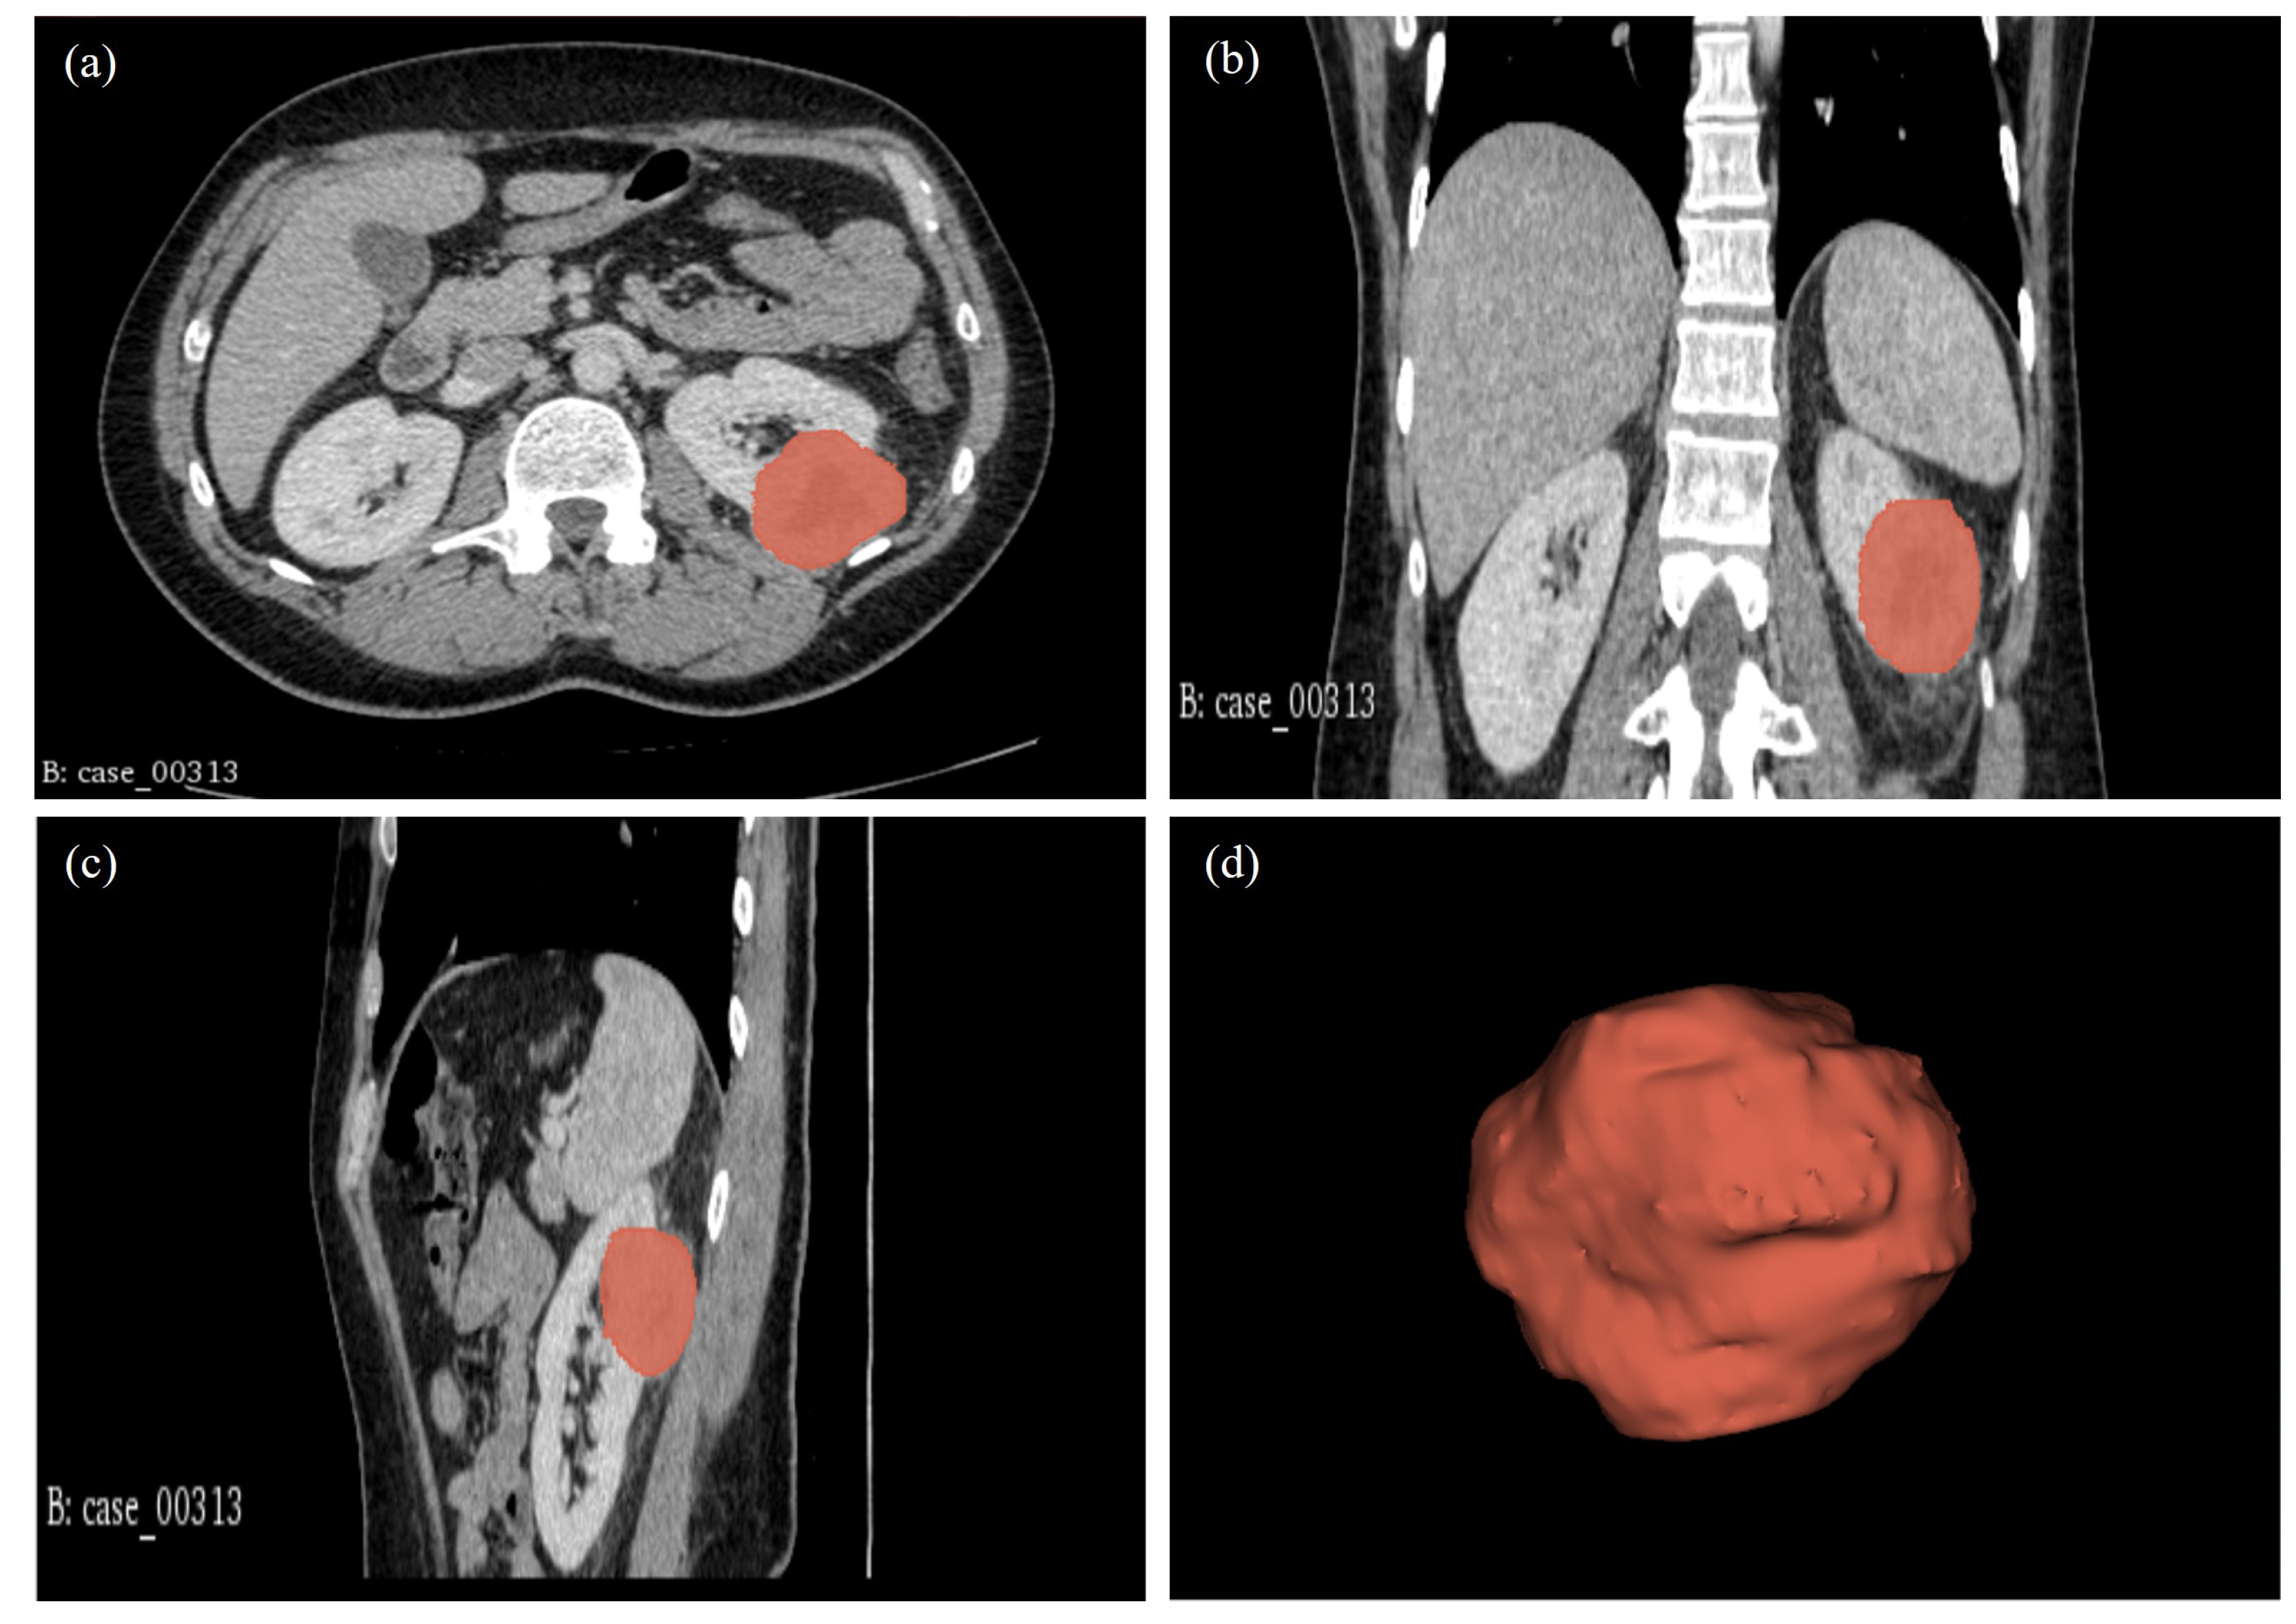

CT image slices for each patient were converted to 3D NIFTI (Neuroimaging Informatics Technology Initiative) format using Python version 3.9. These 3D images were then imported into 3D Slicer software, version 4.11.20210226, for segmentation. Manual segmentation was conducted on the 3D images, delineating the edges of the tumour slice by slice to obtain the volume of interest (VOI) as shown in Figure 9.

Figure 9.

Manual segmentation of the 3D image slices using the 3D Slicer software: version 4.11.20210226. (a) CT scan axial plane; (b) Coronal plane; (c) Sagittal plane; and (d) 3D VOI.